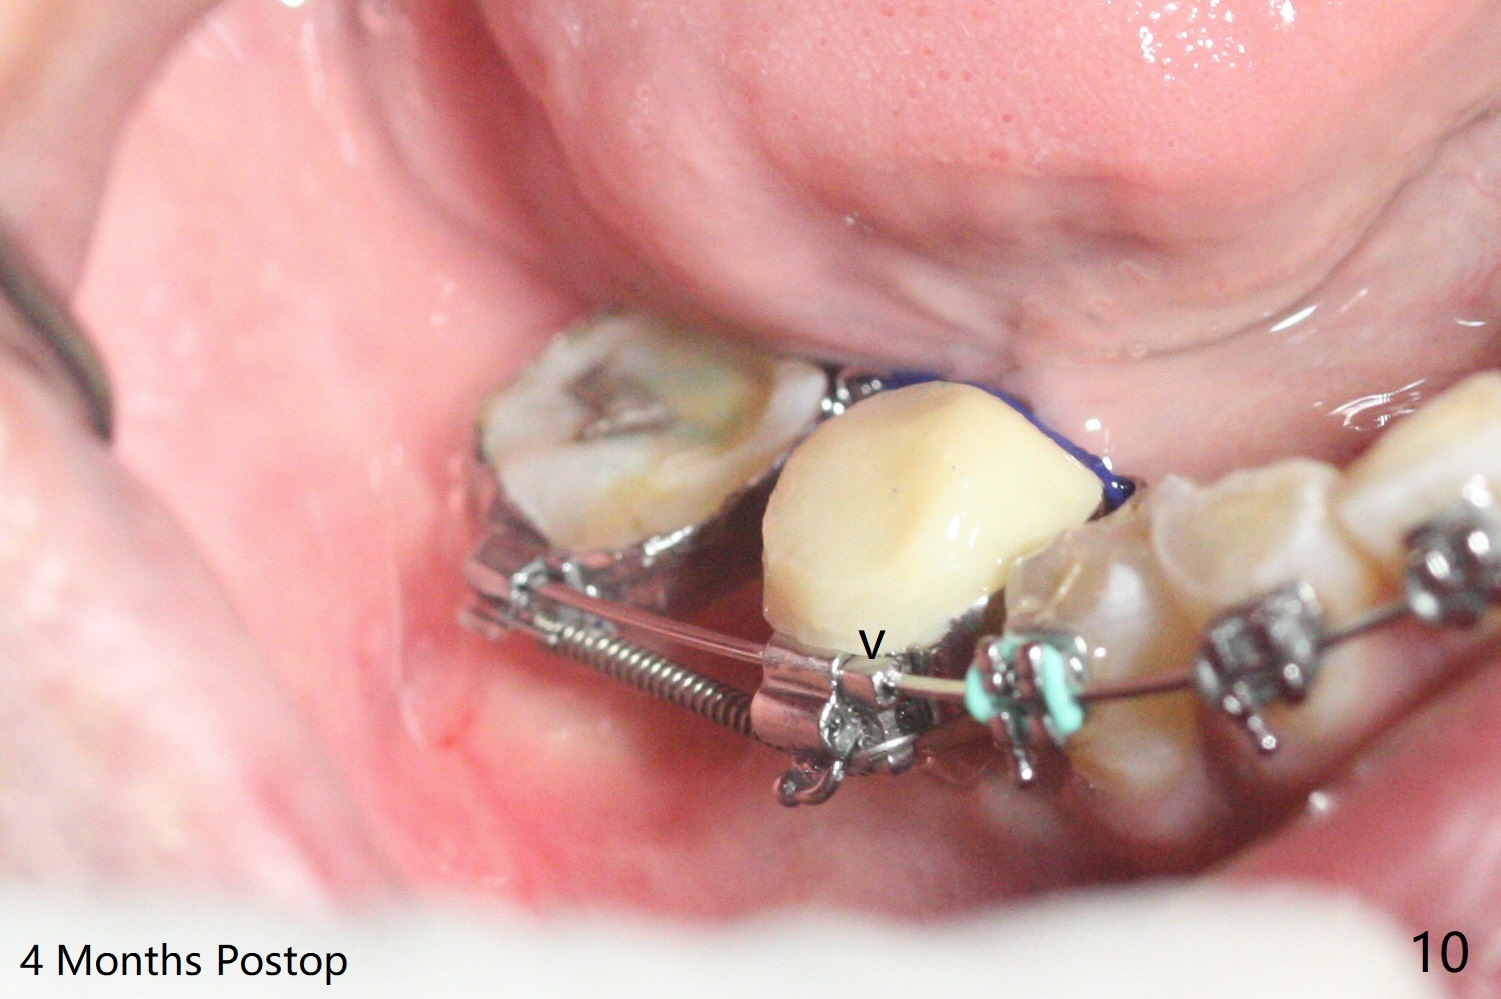

35岁男牙齿矫正后2年5个月右下6远中深龋,拔除后,近中根尖肉芽组织(图零(术前CT冠状切面):*)刮除疼痛,必须阻滞麻醉才能控制疼痛,可能与下牙槽神经分支(图零:红箭头)有关。原先准备在近中牙槽窝近中种植(5x11.5mm),术中发现近中牙槽窝种植好像方便,位置不错,不由自主在那里开始钻洞,由于牙槽窝深,钻洞必须13毫米(图一(接近神经:红虚线)),之后发现钻洞(图二(术前CT3D长轴切面(黑色:近中,远中牙槽窝)):红圆圈)不够理想,使用Lindamann Bur将钻洞往颊侧近中移动(图二:箭头),最终在这方面结果可以(图三,三’,四),虽然接近神经,术后没有神经麻痹。放置粘性骨粉(图四:*),PRF膜,4-0 PGA缝线(图五),最后使用树脂敷料(图六:A)。后牙垂直空间少,术后一周需要降低树脂敷料高度(图七)。术后一个月取出敷料,牙槽窝愈合,植体平台远中稍微暴露(图八),准备一个月后制作临时牙冠。术后两个月植体远中没有暴露,但是基台远中边缘太高了(图九:>),换成6x4毫米愈合基台。下个月换成袖短的修复性基台,安置临时牙冠,牵拉7。舌侧cleats之间放置power chains,颊侧power hooks。其实术后4个月安置临时牙冠和band(图十),牙冠牙合面加高,这样7可以无阻挡移动(图十一:*;16x22 arch wire)。7远中放置power hook行不通,因为末端碰到颊侧前庭牙龈,造成创伤。只好用7颊侧原有牵引勾,在6近中安置一个短的power post (? 图十:箭头),按常规post往下,之间放置12毫米closed spring。如果post往上安置,7牙根牵引可能更有效?近中牵引一个月,第二磨牙前移大约2毫米(图十二:^),稍微近中倾斜,closed spring从12毫米更换到9毫米,舌侧换新的power chains x 4。下一个预约,用sensor 1拍摄根尖片证实第二磨牙近中倾斜,然后在它远中16x22钢丝安放power hook,下缘向颊侧弯曲,避免接触接触粘膜。